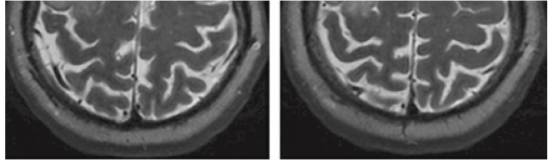

图2. 基底部位于皮层且无增强的低级别胶质瘤的典型影像学表现。 MRI T2加权像上表现为高低混杂信号并伴有点状钙化,这符合少突胶质细胞瘤的诊断。

术后注意事项

术后48小时内进行MRI检查,评估肿瘤切除程度。对本次手术操作进行审慎的的,诚实的,细致的回顾对提高术者的肿瘤切除技能是必要的。